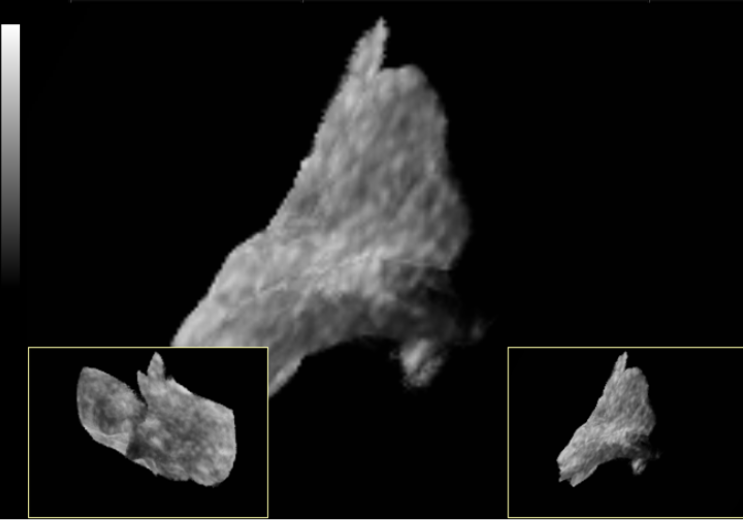

Obr.5

Tear of meniskus (cross dissection) space roconstruction

Obr. 5

Léze menisku –prostorová rekonstrukce trhliny.